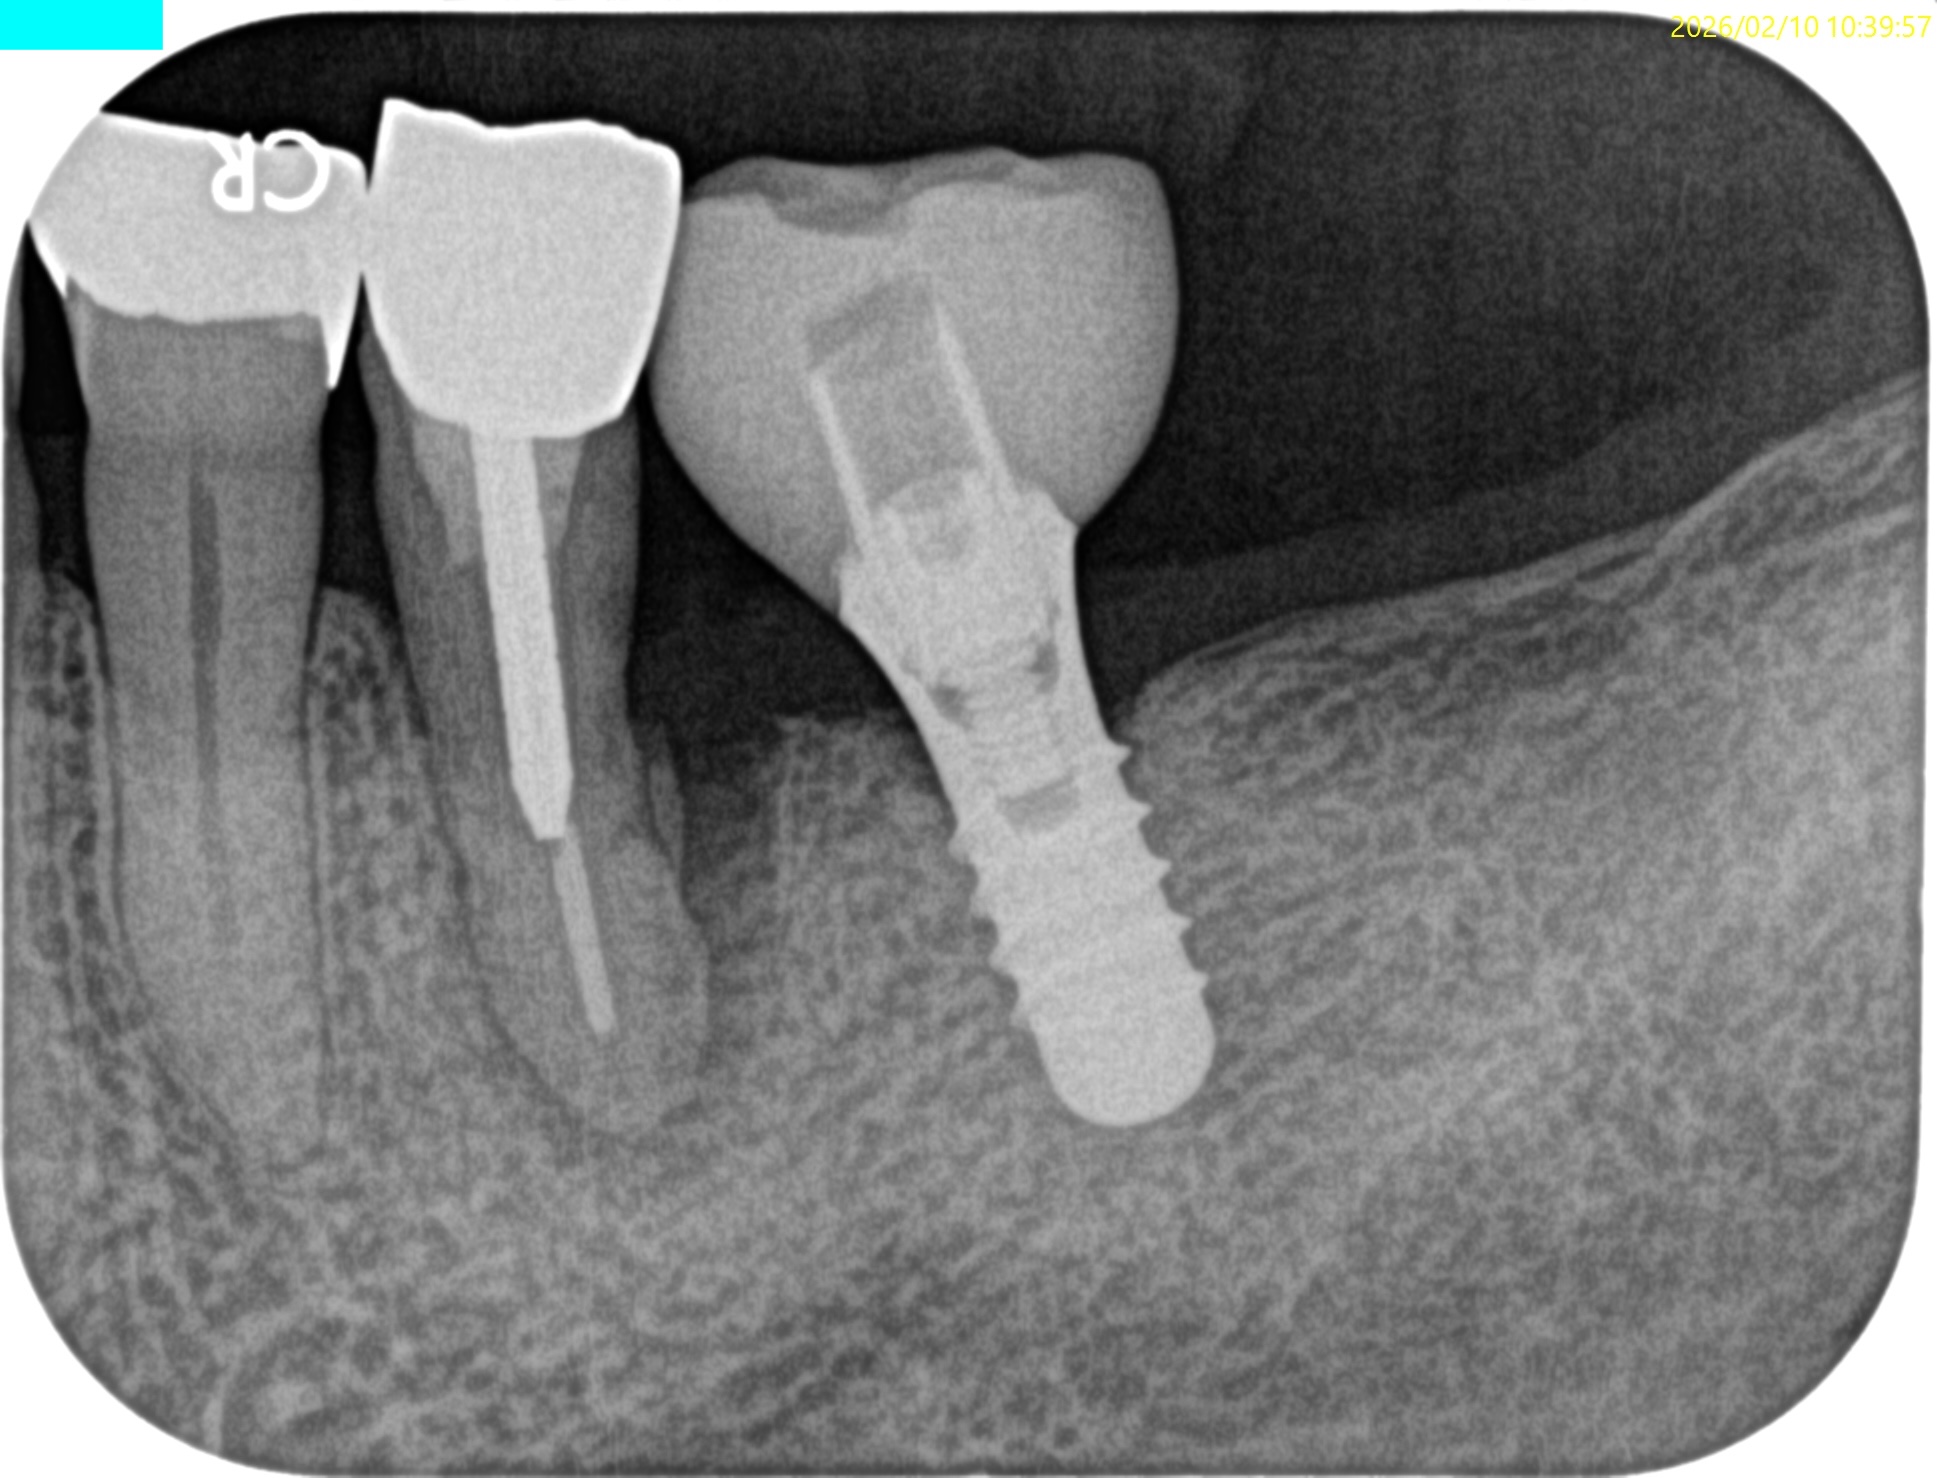

Pre-op Endo test(2026.2.10)

#20は長いピンが装着されており除去に著しく長い時間がかかることが予想される。

この後、ようやくコア用レジンとFiber Postで築造し、術後にPAを撮影した。

見事スクリューピンを除去し支台築造した。